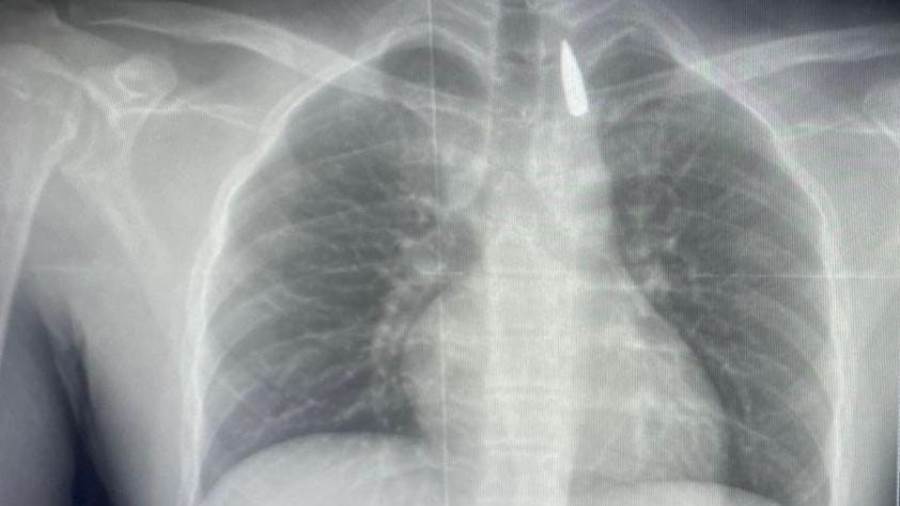

وأوضح الدكتور تامر عبد الله، عميد كلية الطب ورئيس مجلس إدارة المستشفيات الجامعية، أنه في يوم 21 أكتوبر 2025 تمكن فريق من أطباء قسم جراحة القلب والصدر والتخدير والمعاونين من إجراء جراحة دقيقة بالغة الخطورة لأحد المرضى المحجوزين من قطاع غزة، والذي كان قد تعرض لإصابة بطلق ناري في الرأس منذ فترة، استقر المقذوف إثرها داخل تجويف القفص الصدري قرب الشريان الأورطي، وهو أكبر وأهم شرايين الجسم والمسؤول عن تغذية جميع الأعضاء الحيوية.

وأضاف أن الفريق الطبي، رغم دقة الحالة وتعقيدها، نجح في استخراج المقذوف بأمان بعد عملية جراحية نادرة استمرت عدة ساعات داخل المستشفى الجامعي الجديد، حيث خضع المريض بعدها للرعاية الطبية اللازمة، وحالته حاليًا مستقرة وتحت المتابعة الدقيقة من الفريق المختص.